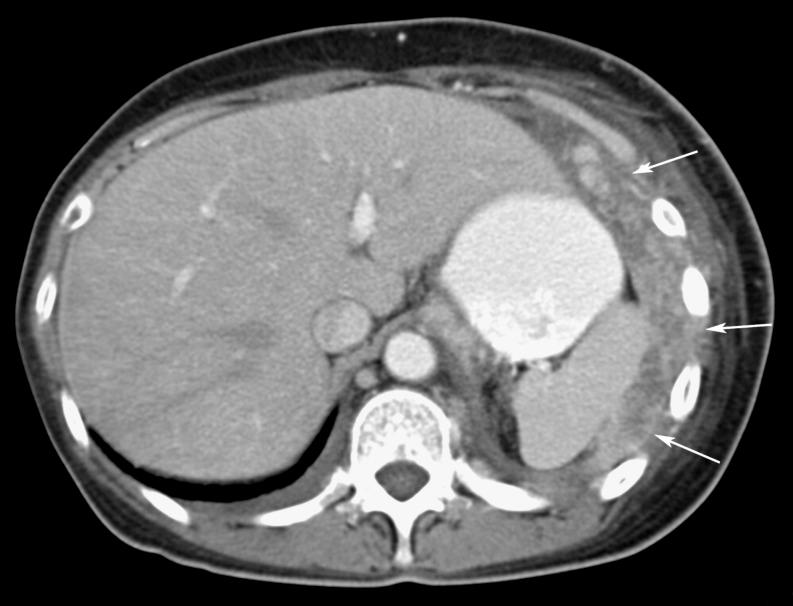

Omental cakes typically are associated with ovarian carcinoma, as this is the most common malignant aetiology. Nonetheless, numerous other neoplasms, as well as infectious and benign processes, can produce omental cakes. METHODS: A broader knowledge of the various causes of omental cakes is valuable diagnostically and to direct appropriate clinical management. RESULTS: We present a spectrum of both common and unusual aetiologies that demonstrate the variable computed tomographic appearances of omental cakes. CONCLUSION: The anatomy and embryology are discussed, as well as the importance of biopsy when the aetiology of omental cakes is uncertain.